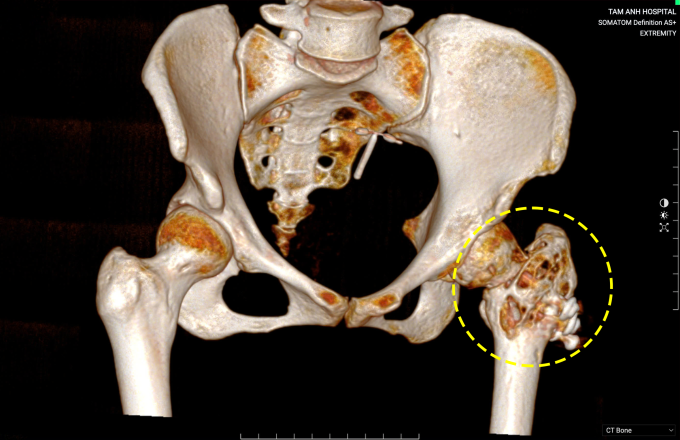

Kết quả chụp X-quang và CT phát hiện cổ xương đùi trái bệnh nhân có vết gãy chưa liền, trên nền tổn thương dạng tiêu xương lan tỏa với thành xương mỏng, không giống nang xương đơn độc (vốn kín, không làm tiêu xương và mỏng thành). ThS.BS Nguyễn Quang Tôn Quyền, Phó trưởng Khoa Chấn thương Chỉnh hình, lấy mẫu xương ở cổ xương đùi và mấu, xét nghiệm hóa mô miễn dịch xác định chị Lan mắc u tế bào khổng lồ tại xương.

Ảnh chụp CT cho thấy chỏm đùi trái chị Lan tiêu xương nặng do u tế bào khổng lồ. Ảnh: Bệnh viện Đa khoa Tâm Anh

Chị Lan có u tế bào khổng lồ ở cổ xương đùi và khối mấu chuyển xương đùi trái gây gãy xương. Bác sĩ Quyền cho rằng u tiến triển cản trở quá trình liền xương dẫn đến biến dạng đầu trên xương đùi sau phẫu thuật lần trước. Khối u đã phát triển rộng, nếu chỉ cắt khối u, ghép xương và kết hợp xương vẫn có nguy cơ thất bại. Do đó, bác sĩ phẫu thuật loại bỏ triệt để u, ghép xương tự thân và thay khớp háng nhân tạo toàn phần để phục hồi vận động cho người bệnh.